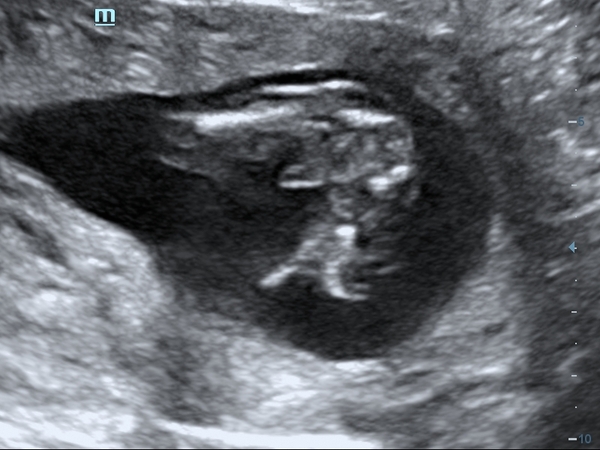

Hello, this is my first post. I'm currently 17+5 weeks pregnant, I had an early gender scan at 14 weeks, the lady turned the tv off to concentrate when checking what gender my baby was? She then passed me a card that said boy and this picture attached. Why does everyone make of this picture? I've looked and looked and I just can't see it. I have a four year old little boy and looked nothing like this when I had his gender scan. I understand it's still very early to check the gender and also that it will look different at 14 week, but When I zoom in I can see something else and not what a boy would have, im waiting for the 20 week scan to buy anything. Also this pregnancy is so different to my sons, with my son my hair and skin were amazing, I've never suffered with acne or spots, and this pregnancy my hair is snapping off, it's so brittle, my face is so sore and covered in painful lumps and the morning sickness was something else😩 thank you

Surprised anyone gave you this scan at 14 weeks. 16 weeks is usually the earliest. It definitely looks like a boy to me though, I don't see the 3 lines for a girl. But I would agree that waiting until 20 weeks would be best, or even having another gender scan elsewhere if you can afford it as the NHS sonographer won't always be able to tell you.

This is my 3rd boy at 15+6 and looks pretty similar to yours, if only a bit more obvious. Boys are usually pretty unmistakable Grin Congratulations either way!

It was her turning the tv off that made me think something was wrong, she didn't turn it back on either. Didn't let me look, then wrote on the sheet she's 85% sure it's a boy, obviously still quite high but still room for it to change, just wanted to see if anyone had a scan that looked like this, I couldn't make sense of it at all x

Definitely a boy! Here is my little girl scan attached at 16 weeks so you can compare.

It really depends on the babys position at the time, sometimes they can tell as early as 12 weeks.

Your photo does look like a boy, and it can be clear at 14 weeks - as it seems to be in your case. Some can be less clear, babies positioning really matters. It’s early; but I’d be fairly confident in that result… it’s fairly common for sonographers at private scans to turn off the screen and write the result down for you, too.